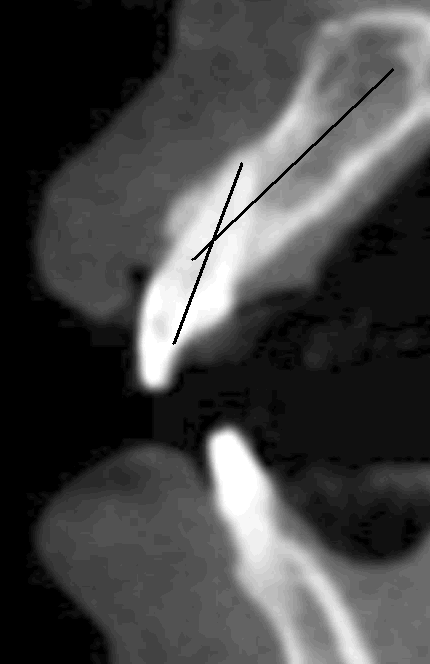

Fig.8 The long axes of the tooth #9 and the alveolar ridge are not coincided. That is, the root of the central incisor is not inserted into the middle of the ridge. For implant stability, we need to place the implant in the middle of the ridge. Back the main text